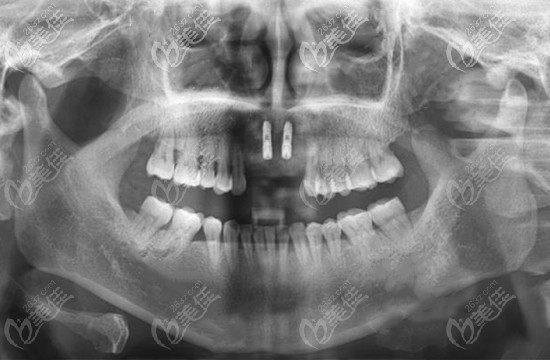

在做了咨詢了解了韓國種植體的品牌后,王女士落定選擇了奧齒泰種植體,之后閆路醫(yī)生結合王女士的CT片以及全面的口腔檢查,為其制定了種植方案。

因為是連續(xù)缺了四顆牙,考慮到其牙槽骨情況還可以,就為其種植了兩顆種植體,之后安裝上連橋冠。

門牙缺失四顆種植案例圖片